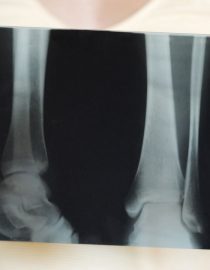

Studies suggest that bone loss can occur simply from having lupus SLE. It is thought that inflamed blood vessels can block the flow of blood to the bones, causing them to weaken and therefore osteoporosis to develop. Those who don’t have their bone density scanned often can have no idea they are suffering from osteoporosis until they experience a fracture.

The SLE Lupus Foundation of New York reminds us that the risk of osteoporosis is very real, even in young women who feel they are not old enough to develop it. They say that 50 percent of those with lupus who break a bone from osteoporosis are under the age of 50. That is a staggering statistic!

Additionally, as a lupus patient, talk to your doctor about having a bone density scan done every year or so. This will mean you can catch thinning bones much earlier on and you won’t be caught by surprise with a nasty fracture. Instead, you can be armed with your information, ready to keep your bones healthy!